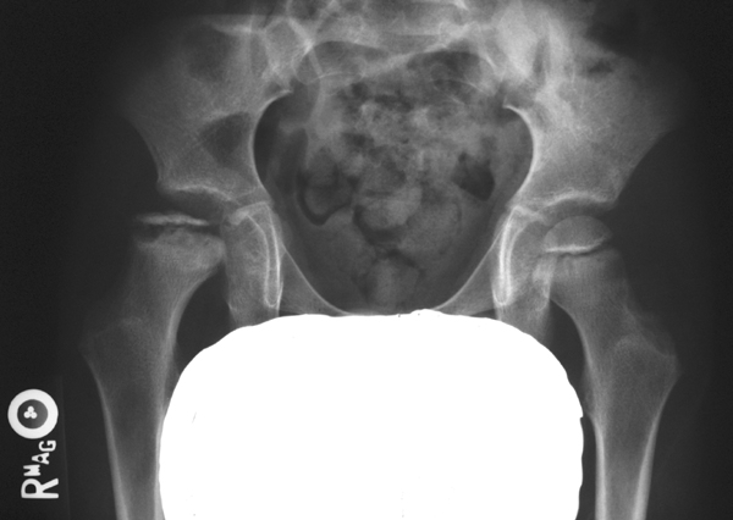

What stage is this disease at?

Stage 4

What are the four stages of Legg-Calvé-Perthes disease?

Avascular: ↓ head size, widened joint space. 2. Fragmentation: bone fragments, crescent sign, blurred outline. 3. Repair: revascularization, new bone, wide short neck. 4. Healed/Deformity: flattened, enlarged head, widened neck, enlarged GT.